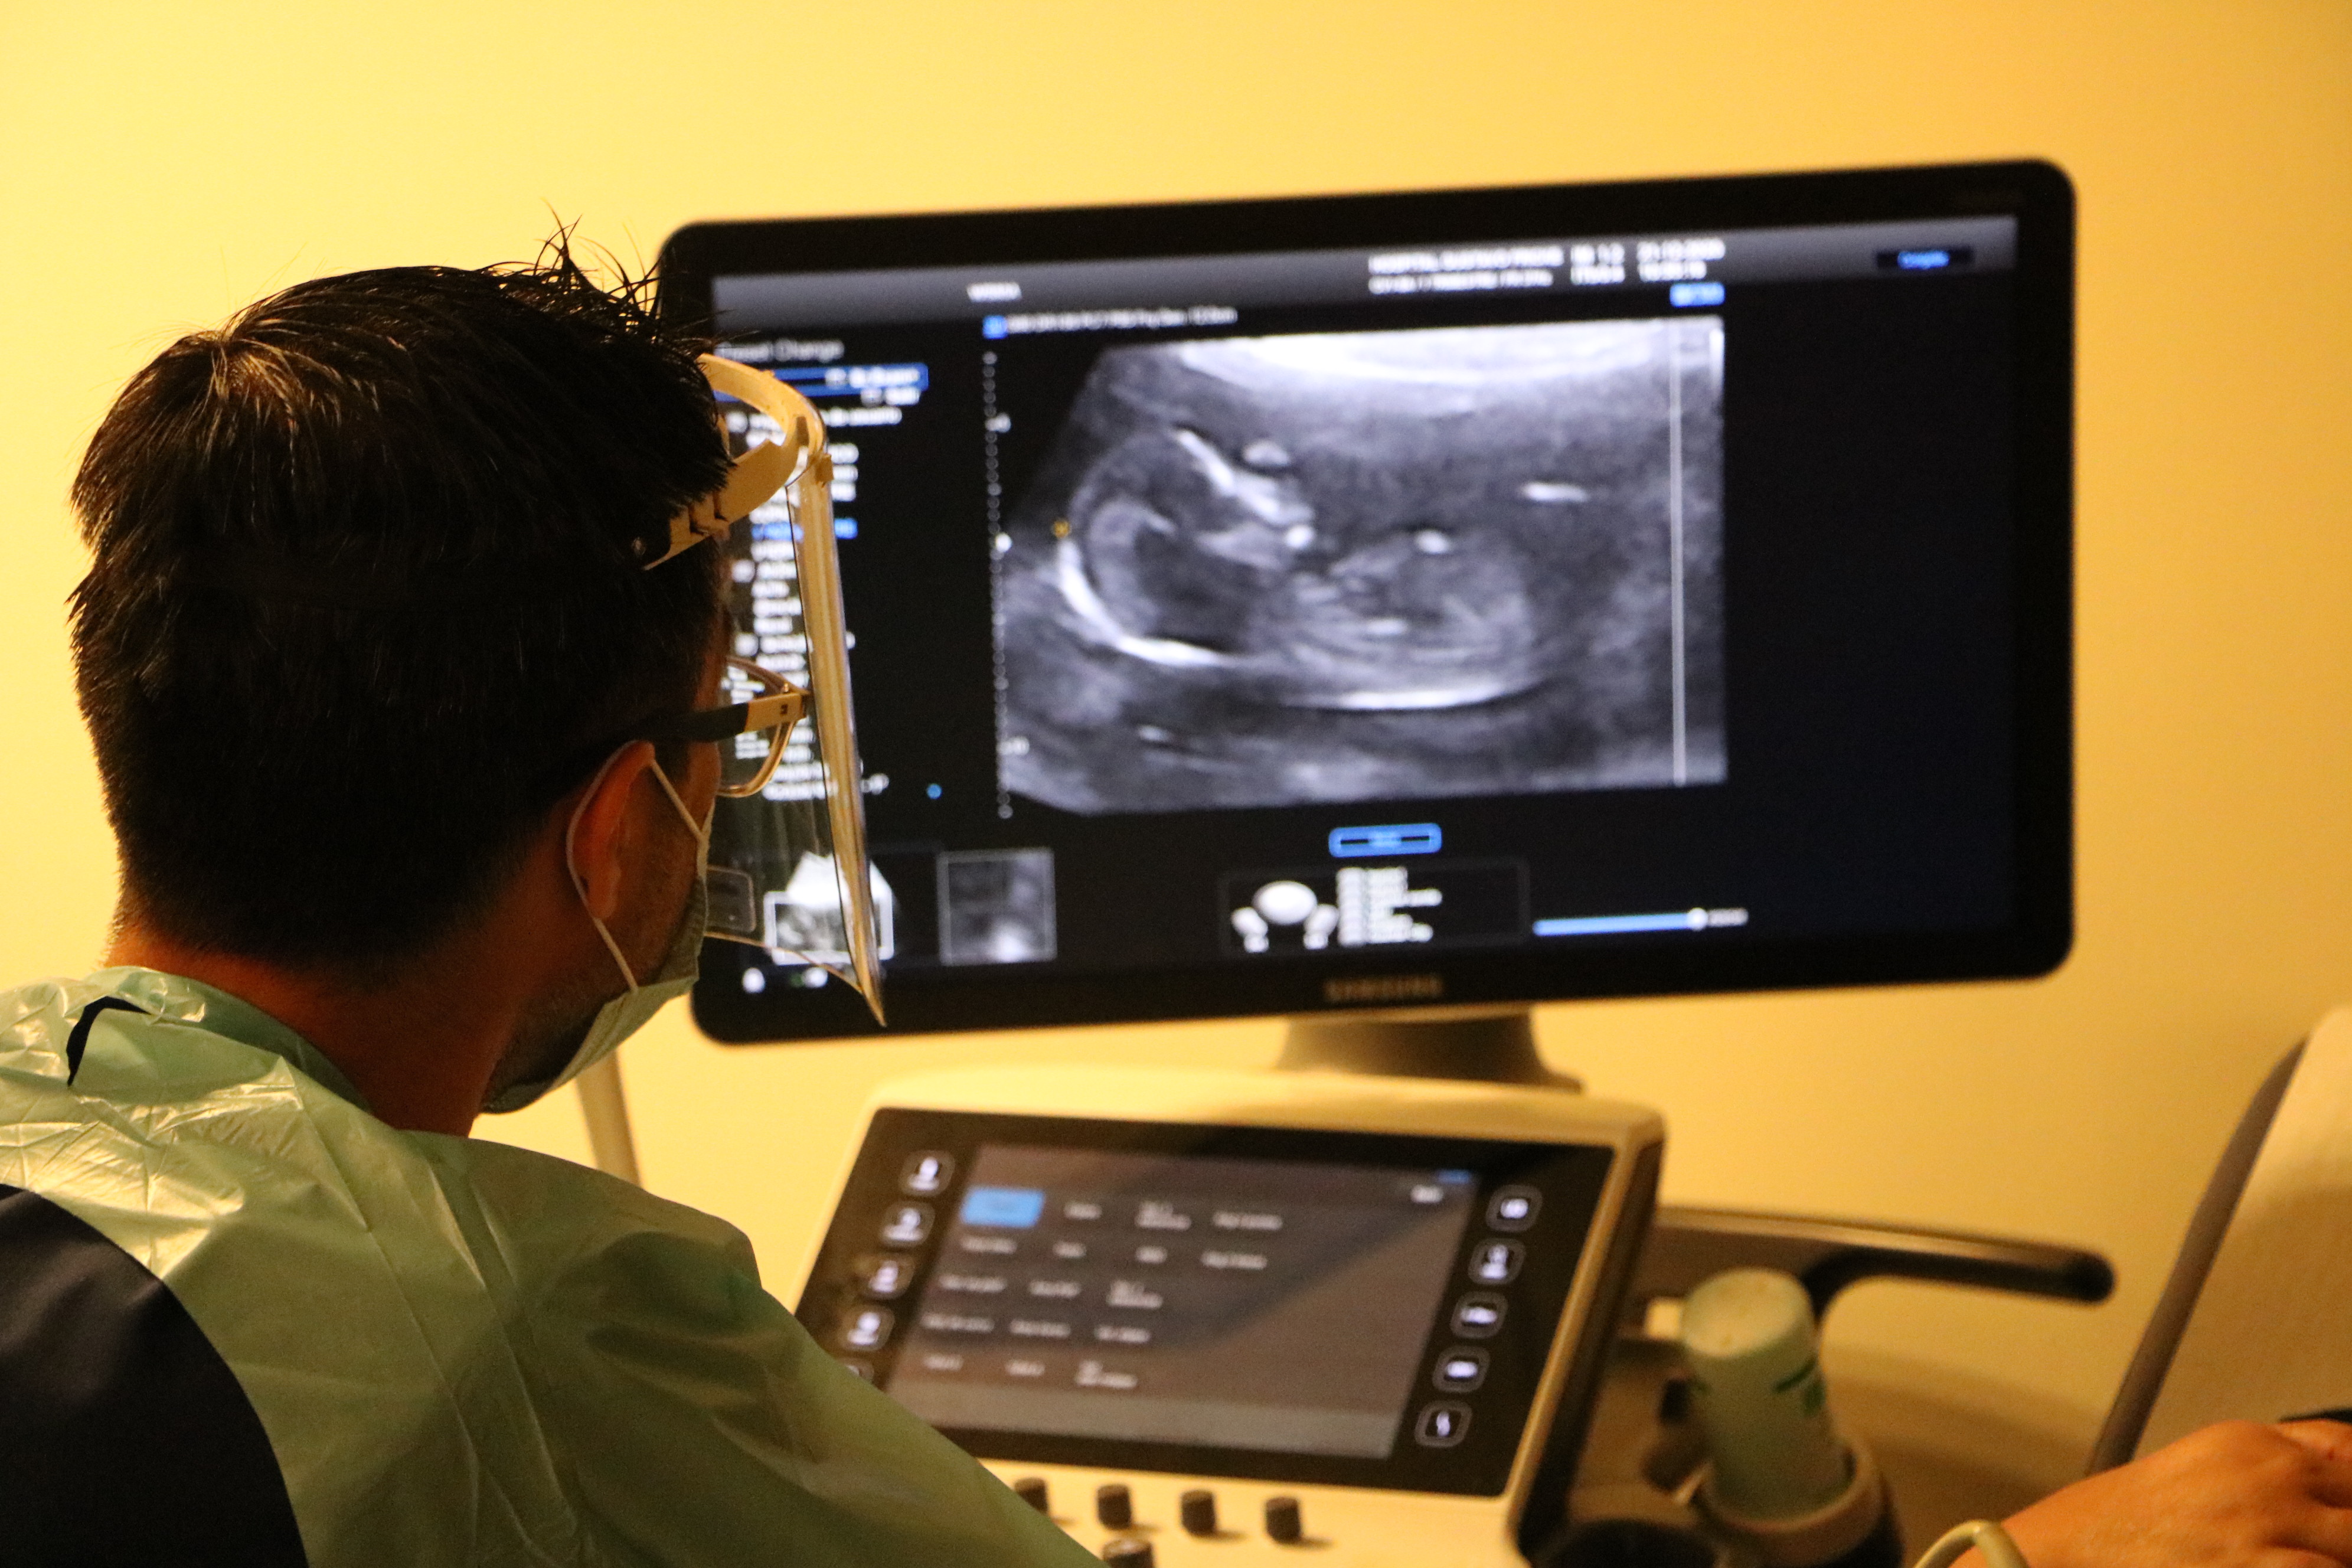

El Dr. Gabriel Anwandter, jefe de la Unidad de Medicina Fetal agrega que “en lo personal, es una tranquilidad poder trabajar en un espacio físico mucho más adecuado y grande, con un mayor respeto a la capacidad que tengamos nosotros de ofrecer las consejerías a las pacientes en un espacio que dé tranquilidad, el silencio del espacio físico en sí nos permite tener una interacción mucho más adecuada y de respeto a la situación de los embarazos con problemas”. El especialista destacó que “la posibilidad de resolver condiciones de salud de mejor manera, el mejor diagnóstico al tener equipamiento nuevo, la posibilidad de interactuar con otras especialidades que están dentro de este mismo sector de procedimientos, como son los cardiólogos pediatras y los mismos neurólogos infantiles”.

El especialista puntualizó que el beneficio mayor es para las pacientes, dado que “las ecografías son largas. Las mujeres embarazadas cuando están en posición acostada a veces se ahogan un poco, sobre todo en embarazos que son múltiples, ahora tenemos la posibilidad de tener aire acondicionado adecuado que permite que podamos manejarlo acá mismo”, y agregó que “afortunadamente, nosotros tenemos un equipo nuevo de ecografía, de última generación, que nos permite hacer diagnósticos de mucha calidad, preservar las imágenes y poder analizarlas a posteriori, creo que se da una situación mucho más adecuada en el contexto de la medicina del siglo XXI”.